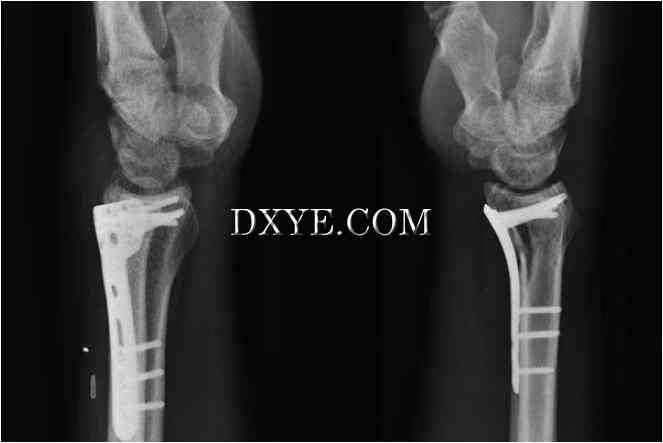

切开复位内固定。开放复位和钢板固定可以直接减少骨折,维持固定的减少,并伴随着固定时间的缩短和腕关节功能的恢复。 已经描述了掌侧桡骨的背侧和掌侧入路。 背侧入路采用与Lister结节一致的纵向切口。 第三个伸肌室打开,拇长伸肌(EPL)皮下移位。 第二和第四隔室从远端半径升高以露出骨折。 掌侧入路采用桡动脉与桡侧屈肌腱(FCR)之间的标准亨利方法,保护FCR尺侧的正中神经的掌侧皮肤分支。 拇长屈肌(FPL)尺骨缩回,前旋方向(PQ)沿桡骨径向切开,作为尺骨瓣增高以暴露骨折。

传统上采用背侧入路,因为这使得板块支撑背部移位的骨折。背侧入路可以直接观察关节面,可以同时治疗腕掌韧带损伤,是背部剪切骨折不可或缺的部分。由于骨 - 骨头更薄且经常粉碎,所以从背部移植骨也更容易。然而在20世纪90年代后期和21世纪初,背板失宠,因为早期的背板与软组织并发症相关,因为伸肌腱与桡骨远端接近。这导致肌腱刺激或破裂,并且通常需要常规移除板或其他程序。另外,使用非锁定背板后的早期运动可能会导致远端螺钉松动,特别是骨干旋转的干骺端粉碎患者。然而,与手掌钢板相比,新型的低位背侧锁定钢板在保持复位后骨折固定方面同样有效,而不会增加并发症风险(图76.15)。

目前,绝大多数手外科医生偏好大部分桡骨远端骨折的手掌入路(图76.16)。 PQ在植入物和屈肌腱之间形成屏障,使肌腱并发症发生率最小化。 锁定螺钉的固定角板能够更有效地保持下降,提供软骨下支持,即使存在骨质疏松性骨质,也能抵抗二次移位。 与背侧平皿法相比,对骨移植的需求减少。 手掌入路不可能直接观察到关节面,必须注意不要将手掌腕韧带从桡骨远端抬起。 平皿法不是没有并发症。 不正确放置的板可能会导致板的远端边界处的FPL的刺激和破裂。 螺丝尖端过度会导致伸肌腱断裂。 也有远端软骨下螺钉穿透关节的风险。

15.jpg

图 76.15.  在一个粉碎的关节内桡骨远端骨折患者(AO C3型)中使用低位背侧锁定钢板。

16.jpg

图 76.16.  使用低剖面的掌侧锁定板来解决局部关节的桡骨远端骨折(AO B3型)。